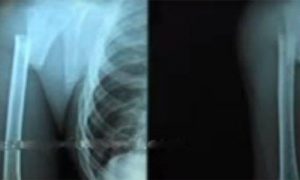

വെള്ളിയാഴ്ച ഫിസിയോ തെറാപ്പിക്ക് എത്തിച്ചപ്പോൾ തന്നെ, ഡോക്ടർ ഇവരോട് കുട്ടിയെ കൃത്യമായി ഫിസിയോ തെറാപ്പിക്ക് വിധേയനാക്കുന്നില്ലേ എന്ന് ചോദിച്ചിരുന്നതാണ്. കാസർകോട് പ്രാഥമിക ആരോഗ്യ കേന്ദ്രത്തിൽ പോലും ഫിസിയോ തെറാപ്പി ലഭ്യമെന്നിരിക്കെ അബ്ദുൾ റസാഖ് ചികിത്സയ്ക്ക് വിധേയനായിട്ട് മൂന്നു മാസം എങ്കിലും ആയിട്ടുണ്ട് എന്ന് ഡോക്ടർ അവരോട് തറപ്പിച്ചുപറഞ്ഞു. പിന്നീട് സംഭവങ്ങൾ നടക്കുന്നത് കഴിഞ്ഞ തിങ്കളാഴ്ചയാണ്. ഫിസിയോ തെറാപ്പിക്ക് വിധേയനാക്കിയ തന്റെ കുട്ടിയുടെ കാല് ചികിത്സക്കിടയിൽ ഒടിഞ്ഞു എന്ന് ആരോപിച്ചുകൊണ്ടായിരുന്നു രക്ഷിതാക്കളുടെ വരവ്. ആശുപത്രി അധികൃതർ ശക്തമായി ഇത് നിഷേധിച്ചപ്പോൾ, ചികിത്സ ചെയ്തശേഷം ഇവർ മടങ്ങിപ്പോയി. അതിനുശേഷം രക്ഷിതാക്കൾ കുട്ടിയുമായി ബുധനാഴ്ച വീണ്ടും വന്നു തങ്ങളുടെ കുട്ടിയുടെ കയ്യും കാലും ഫിസിയോ തെറാപ്പിക്കിടെ ഒടിഞ്ഞു എന്നായിരുന്നു ആ ആരോപണം. ഈ സമയത്ത് മാതാപിതാക്കള്ക്ക് പിന്തുണയുമായി ഡി.വൈ.എഫ്. ഐ പ്രവര്ത്തകരും മാധ്യമങ്ങളും കൂടെ ഉണ്ടായിരുന്നു. ഇത് വ്യക്തമാക്കുന്നത് ഈ സംഭവം മുന്കൂട്ടി ആസൂത്രണം ചെയ്തതാണ് എന്നാണ്.

തങ്ങളുടെ ചികിത്സയിൽ ഒരു പിഴവും പറ്റിയിട്ടില്ല എന്ന് ഉറപ്പിച്ചുപറഞ്ഞ ഡോക്ടർമാരുടെയും സ്റ്റാഫിന്റേയും നേരെ മാതാവ് കയർക്കുമ്പോഴും വേദനയാൽ കരഞ്ഞിരുന്ന കുട്ടിയെ അവർ ഒരിക്കൽ പോലും പരിഗണിച്ചില്ല എന്ന് ആശുപത്രിയിൽ ആ സമയത്തിൽ ചികിത്സയ്ക്ക് എത്തിയവരും സ്റ്റാഫും പറയുന്നു. കൂടാതെ, കുട്ടിയുടെ അസ്ഥി ഒടിഞ്ഞു എന്ന് പറയുന്ന ഭാഗങ്ങളിൽ അമർത്തിക്കൊണ്ടായിരുന്നു മാതാവ് എല്ലാവരോടും സംസാരിച്ചിരുന്നത് എന്നും ഇവർ പറയുന്നു. ഈ സമയത്തിനുള്ളിൽ ചാനലുകള് ലൈവായി വിഷയം കവര് ചെയ്യുകയും ഏതാനും ഓൺ ലൈൻ പോർട്ടലുകൾ കാസർകോട് ജനറൽ ആശുപത്രിയിൽ എൻഡോസൾഫാൻ ബാധിതനായ കുട്ടിക്ക് ചികിത്സാ പിഴവ് എന്ന രീതിയിൽ വാർത്തകൾ നൽകുകയും ചെയ്തു. ഇതൊക്കെ കാണുമ്പോൾ ഇത്തരത്തിൽ വാർത്ത വരികയായിരുന്നു അവരുടെ ലക്ഷ്യം എന്നാണ് മനസ്സിലാക്കേണ്ടത്. ഇത് വഴി സർക്കാരിൽ നിന്നും ലഭിക്കുന്ന സാമ്പത്തിക സഹായവും ഇവർ കരുതിയിരുന്നു എന്നും സംശയിക്കേണ്ടതാണ്. ജനറല് ആശുപത്രിയില് വാര്ത്താ ബഹളങ്ങള് ശ്രുഷ്ട്ടിച്ച ശേഷം പാര്ട്ടി പ്രവര്ത്തകര് ആശുപത്രി അധികൃതരുമായി സംസാരിക്കുകയും കുട്ടിയെ വിദഗ്ദ ചികിത്സക്കായി പരിയാരം മെഡിക്കല് കോളെജിലേക്ക് കൊണ്ടുപോകുകയും ചെയ്തു. പി. കരുണാകരന് എം.പി, എന്. എ നെല്ലിക്കുന്ന് എം.എല്.എ, സി. പി .എം ജില്ലാ കമ്മിറ്റി അംഗം സിജി മാത്യു എന്നിവര് കുട്ടിയെ ആശുപത്രിയില് സന്ദര്ശിക്കുകയും ചെയ്തിരുന്നു.